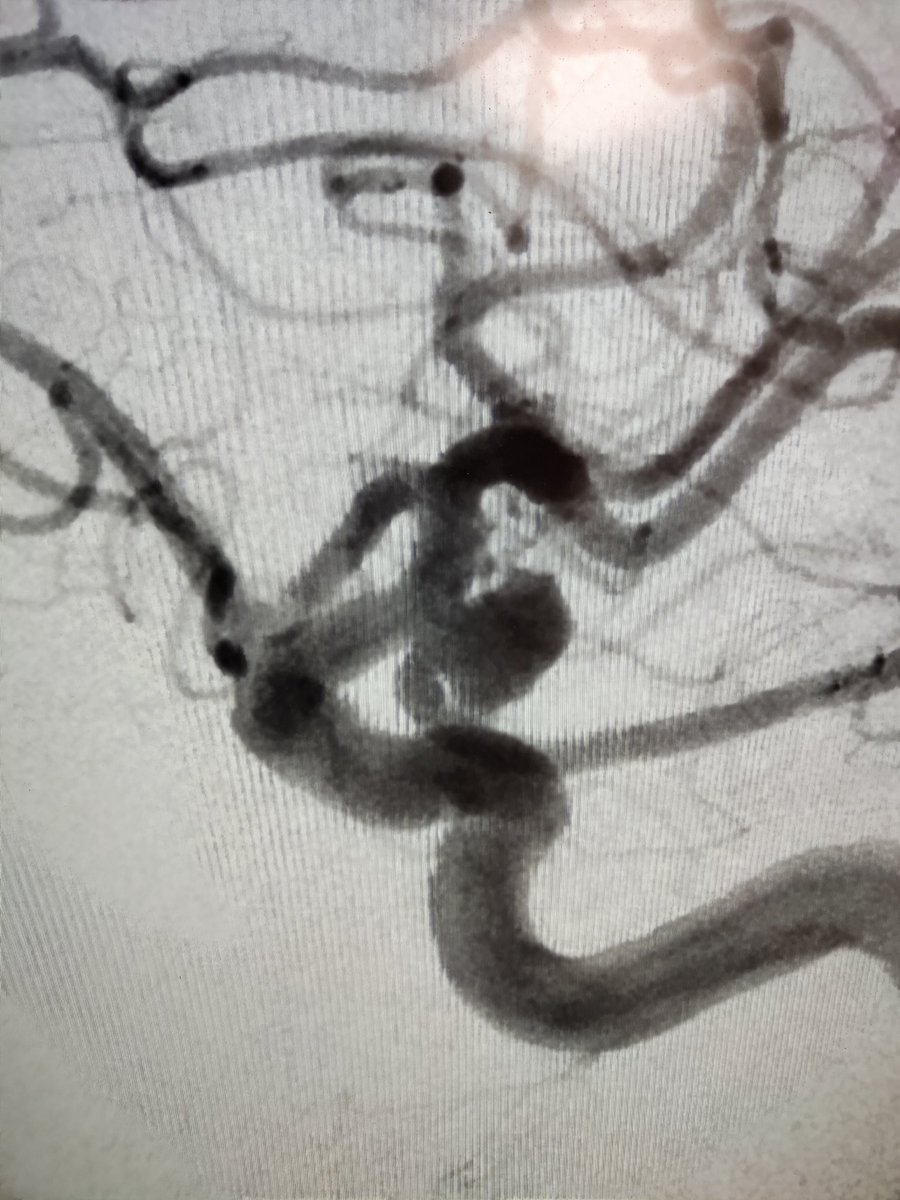

Large MCA Aneurysm w/ both branches arising from the sac + Calcified wide neck #Neurorad #NeuroIrad #neurosurgery #Neurointervention #radres #medtwitter #neurotwitter #meded @WorldMedica How would you treat it??

1

8